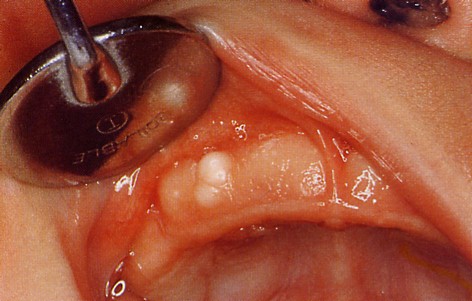

白色ないし黄白色の光沢をもった半球状の硬い、粟粒大から小真珠大の大小の腫瘤としてみられます。

粘膜表面の近くに存在し、歯肉の表面からやや突出しているものが多いです。

2〜3個のものから通常は数多く発生するものが多く、そのために歯肉の表面が著しく凹凸不整の状態になっている

ものが多いです。

症例